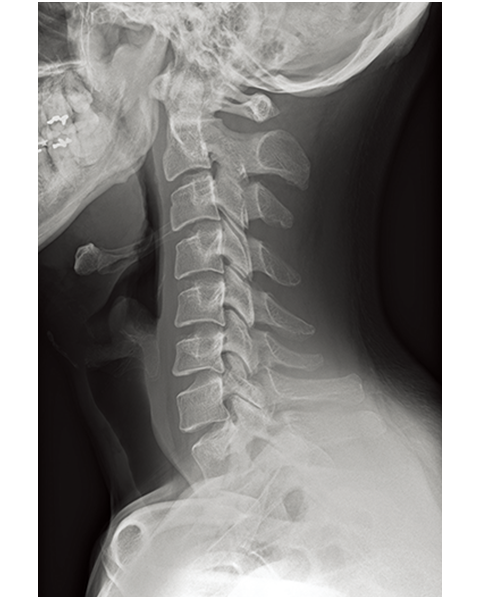

Multiple body parts supported

Abdomen

Cervical Spine

Thoracic Spine

Lumber Spine